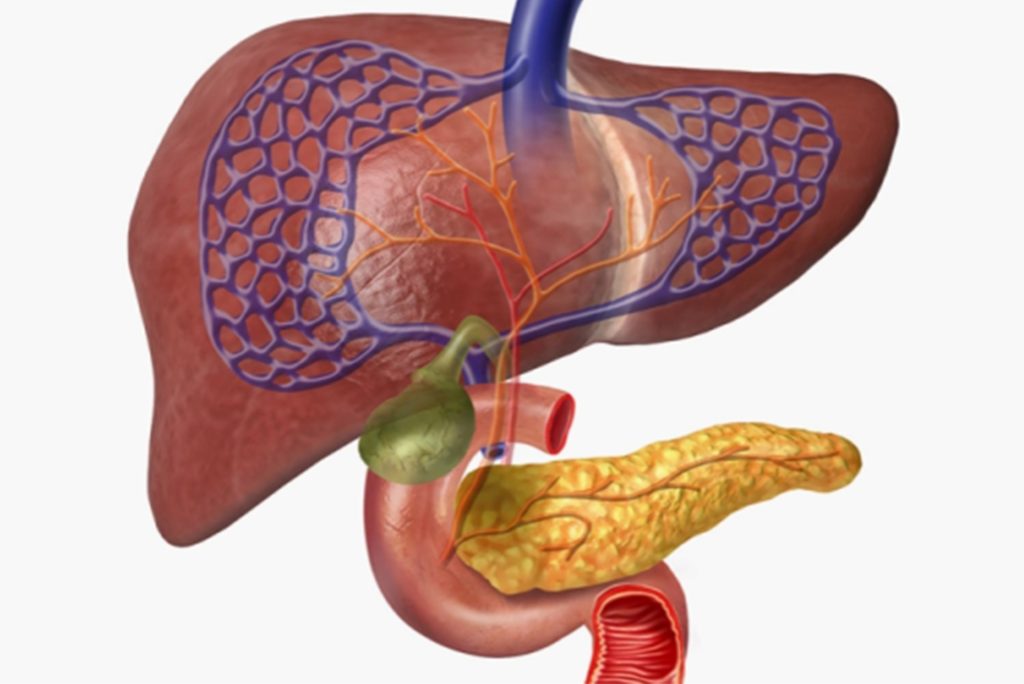

يفرز هذا الهرمون المهم من البنكرياس وينظم نسبة السكر في الدم، كما أنه يسمح للخلايا الموجودة في العضلات والكبد بامتصاص سكر الجلوكوز الموجود في الدم، ما يمنح هذه الخلايا الطاقة، ويؤثر على عمليات الأيض الأخرى مثل كيفية استخدام الجسم للدهون والبروتين.